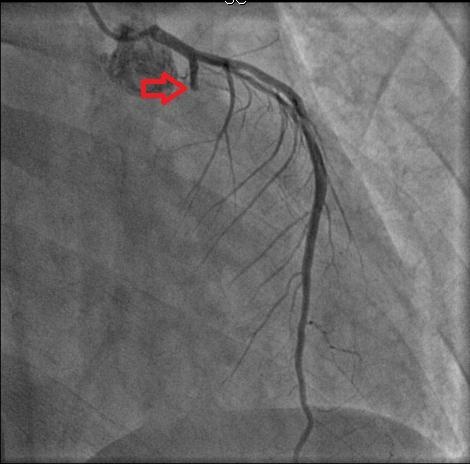

| Hình ảnh chụp mạch vành trước khi đặt stent cho thấy nhánh mũ tắc hoàn toàn từ LCX1. Ảnh: BVCC. |

Qua thăm khám, nam bệnh nhân được chẩn đoán NMCT cấp, viêm cơ tim, chỉ định chụp mạch vành ngay lập tức.

Sau đó, các bác sĩ can thiệp một stent mạch vành có phủ thuốc trên LCX1 cùng liệu trình điều trị chuẩn của NMCT.